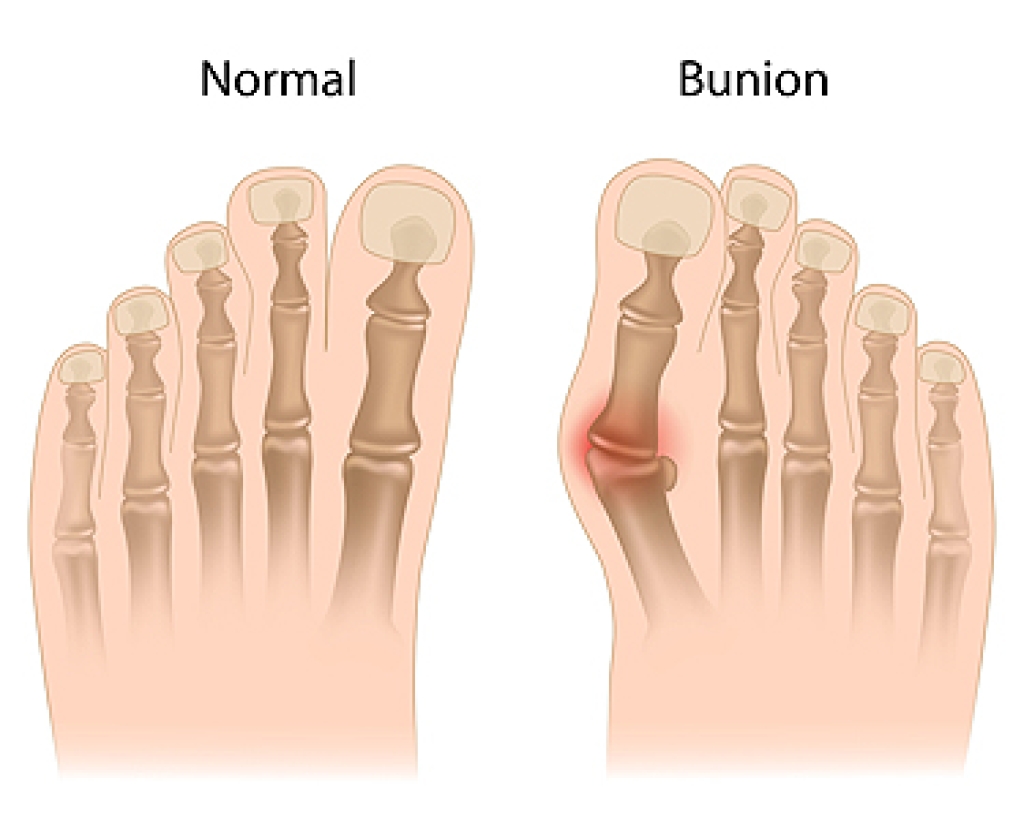

Arthritis in the feet is a condition that can bring a range of discomforts and unique sensations. It often manifests as pain and stiffness in the joints, making every step a potential challenge. Individuals with foot arthritis may experience a deep, aching pain that worsens with movement. This discomfort can be present in various areas of the foot, including the toes, the midfoot, or the ankle. One common sensation associated with foot arthritis is a feeling of stiffness or inflexibility. It can be particularly pronounced in the morning or after periods of inactivity. As arthritis progresses, swelling and warmth may accompany the pain, making the affected foot feel tender to the touch. In more advanced cases, individuals may notice a grinding or popping sensation in the affected joints, indicating the wear and tear of the cartilage. Understanding what arthritis in the feet feels like is essential for timely diagnosis and effective management. If you have any of the above symptoms which may indicate arthritis in the feet, it is suggested that you schedule an appointment with a podiatrist who can guide you toward relief methods.

Arthritis is a term that is commonly used to describe joint pain. The condition itself can occur to anyone of any age, race, or gender, and there are over 100 types of it. Nevertheless, arthritis is more commonly found in women compared to men, and it is also more prevalent in those who are overweight. The causes of arthritis vary depending on which type of arthritis you have. Osteoarthritis for example, is often caused by injury, while rheumatoid arthritis is caused by a misdirected immune system.

Arthritic symptoms range in severity, and they may come and go. Some symptoms stay the same for several years but could potentially get worse with time. Severe cases of arthritis can prevent its sufferers from performing daily activities and make walking difficult.